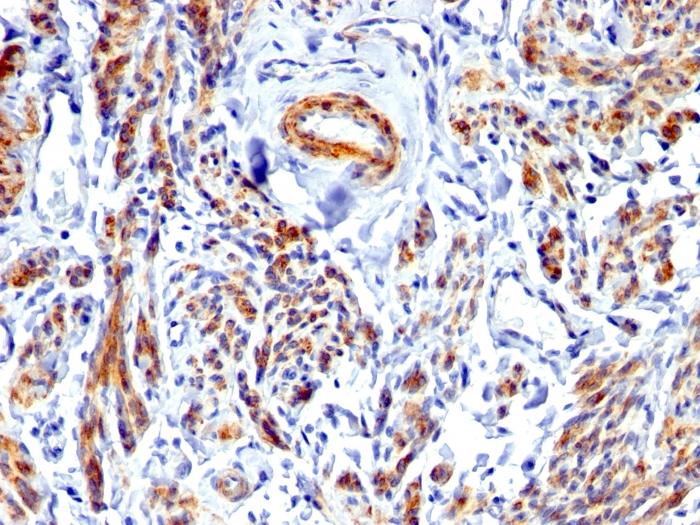

Positive Control

Uterus, Blood vessels in all tissues, smooth muscle or leiomyosarcoma

Antibody target cellular localization

Cytoskeleton|Plasma membrane

Cell tissue expression

Smooth muscle

IHC, FFPE (verified)|WB (verified)

IHC (FFPE) (verified)|WB (verified)